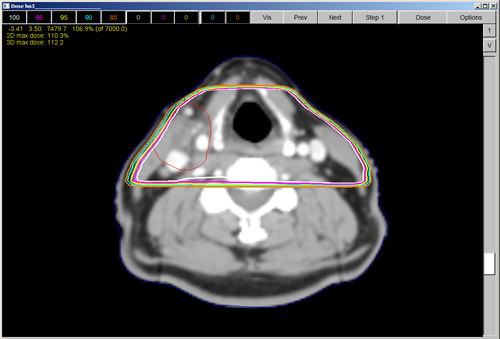

Quiz: Question 1

1) In the treatment plan above, the tumor volume in red was probably planned with; a) AP/PA Fields b) RT/LT Lateral Fields c) A Multi-field IMRT Arrangement d) Electrons